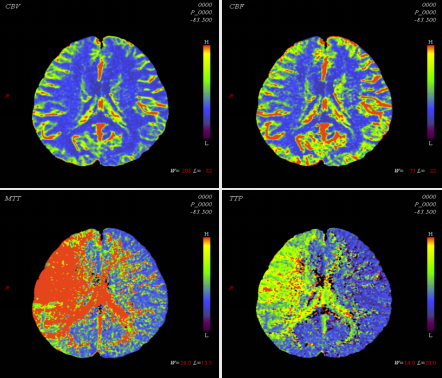

灌注图像后处理结果

CT脑灌注分析参数结果伪彩图(CBF,CBV,MTT,TTP)

MR灌注分析参数结果伪彩图(CBF,CBV,MTT,TTP)